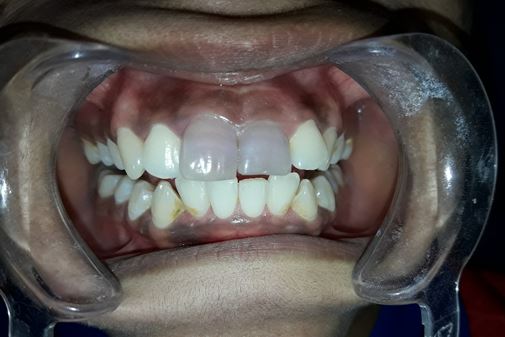

Management of intrinsic discoloration using walking bleach technique in maxillary central incisors

Introduction. Non-vital bleaching is a non-invasive technique to treat the intrinsic discoloration of teeth of several etiologies. Hydrogen peroxide and sodium perborate are commonly used bleaching agents.

Method. Maxillary central incisors were isolated with rubber dam and root canal treatment was performed. Barrier space preparation was done using a heated instrument. Glass ionomer cement was used a barrier material. Mixture of hydrogen peroxide and sodium perborate was placed in the canal and sealed with intermediate restorative material. After 1 week, the procedure was repeated to achieve the desired results.

Conclusion. Non-vital bleaching is a minimally invasive procedure to restore the esthetics of a discolored non-vital tooth. However, care should be taken to prevent any post-operative complications.